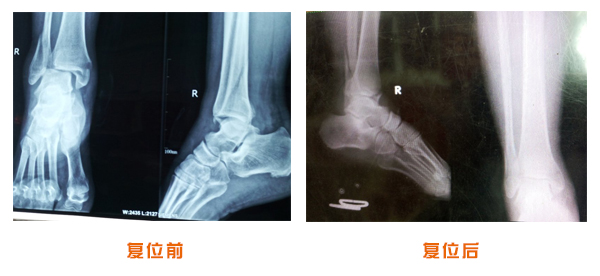

肥城市安駕莊梁氏骨科醫(yī)院是一所以梁氏手法正骨配合膏藥為特色的現(xiàn)代化??漆t(yī)院。

梁氏骨科術(shù)始創(chuàng)于清雍正年間,歷經(jīng)八代,至今已有三百年歷史。據(jù)1929年泰安縣志載“梁瑞圖先生,字增生,號(hào)蓮峰,安駕莊人,精岐黃并發(fā)明接骨,凡跌打車凡跌打車軋皮不破而碎骨者......【詳細(xì)】 |